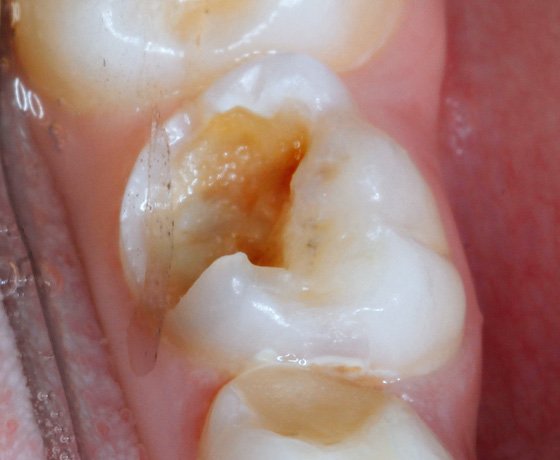

Initial situation: A 10-year-old boy presented with a fractured primary first molar in the mandible. Isolation process is complicated due to copious amounts of saliva.

Lingual involvement of the fractured tooth which is close to the gingival margin